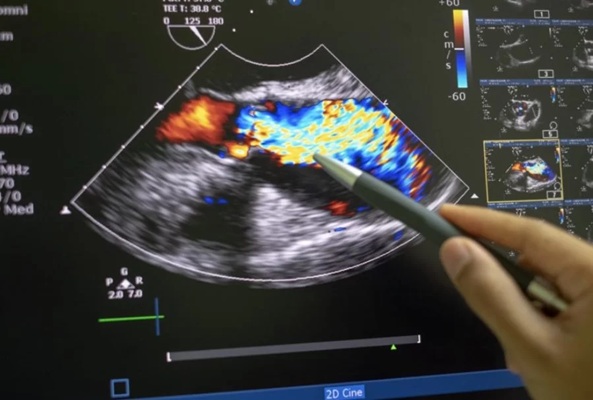

Exame indicado para avaliação detalhada de veias e artérias, permitindo a análise do sistema vascular com alta precisão. Realizada na UltraScan, em Petrópolis, auxilia no diagnóstico de doenças cardiovasculares.

Exame que avalia o fluxo sanguíneo nas veias e artérias, auxiliando na identificação de alterações circulatórias. Na UltraScan, em Petrópolis, é realizado com tecnologia adequada e atenção técnica.

Recurso complementar à ultrassonografia que permite avaliar o fluxo e a direção do sangue nas artérias e veias. Realizado na UltraScan, em Petrópolis, com foco na precisão diagnóstica.